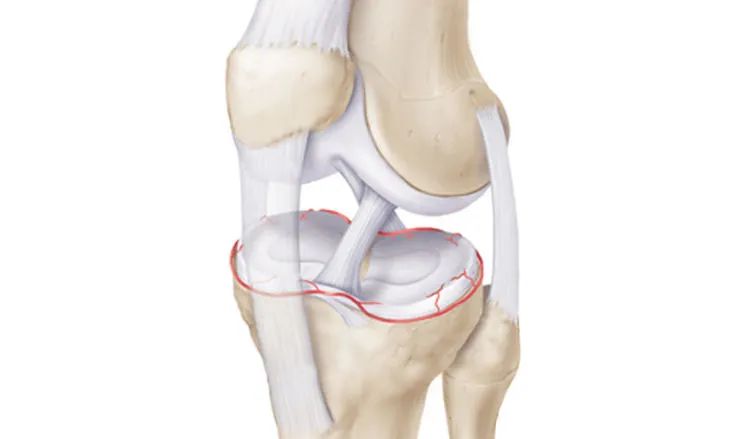

12、半月板外周血管半月板的血供来自于膝下内侧动脉、膝下外侧动脉、膝中动脉、膝上内侧动脉(膝上外侧动脉不参与半月板血供!)、膝降动脉、膝后内侧动脉和膝后外侧动脉,以上这些动脉形成紧绕半月板的周围动脉环。

膝下内侧动脉自后向前经胫骨内侧缘与腘肌上缘的筋膜内走向前侧,至胫骨内侧缘前下方沿内侧半月板外周走行,MR造影下显示血管其实是非常清楚的,大部分的医院不愿意花费太多的时间而已。

膝下外侧动脉在距腓骨小头顶点上方,经腓侧副韧带深面,紧贴外侧半月板外周向前走行,MR上容易将其误认为半月板边缘分离。

膝下内侧动脉、膝下外侧动脉等共同组成血管环,MR轴位上也常常被误诊为半月板关节囊分离,其实两者完全不同。